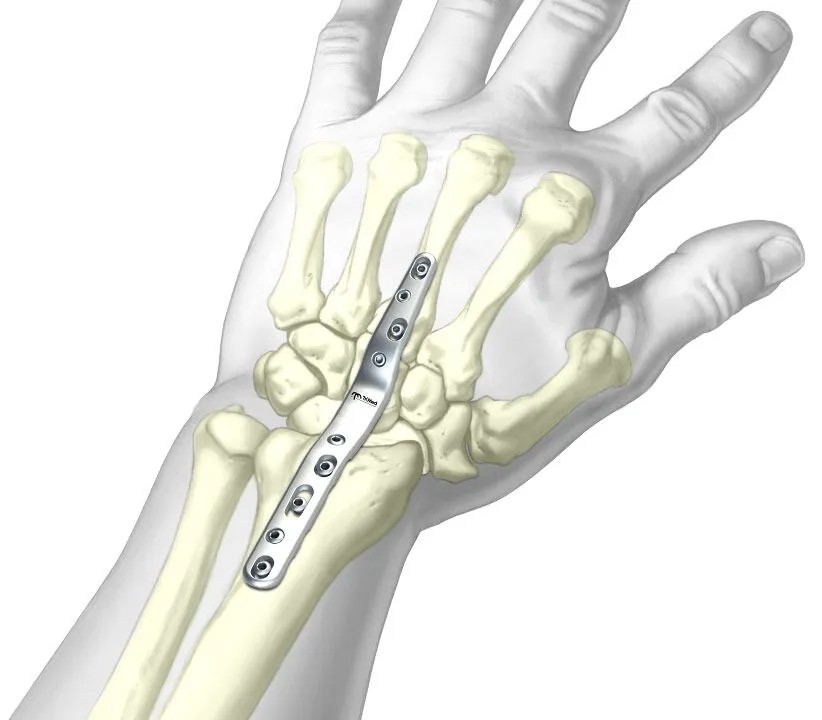

There is a spectrum of surgeries, ranging from relatively conservative to definitive fusion. These include synovectomy and tendon procedures to remove inflamed synovium and protect tendons; partial fusions or proximal row carpectomy to preserve some motion while stabilising the wrist; and total wrist fusion to create a strong, stable platform for grip in the most severely damaged wrists. Total wrist fusion sacrifices wrist motion but can be extremely effective at removing pain.

Figure 6. Dorsal plate used for total wrist fusion, creating a stable, pain-free wrist in advanced rheumatoid arthritis.